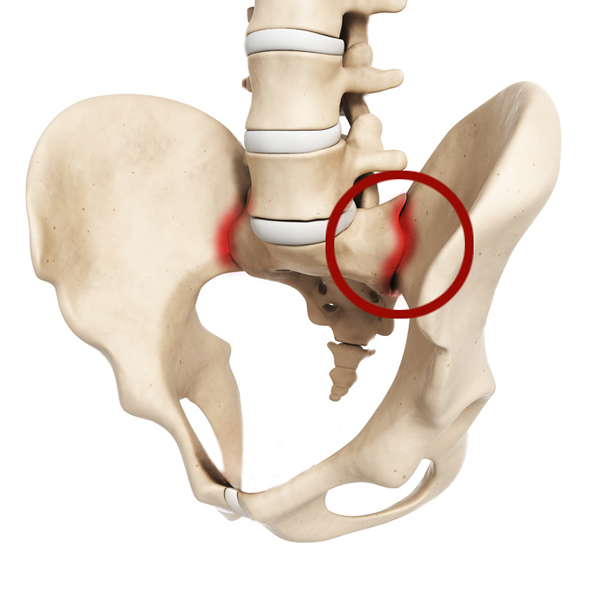

Структура позвоночника: сегменты и тазовые отделы в фотографиях